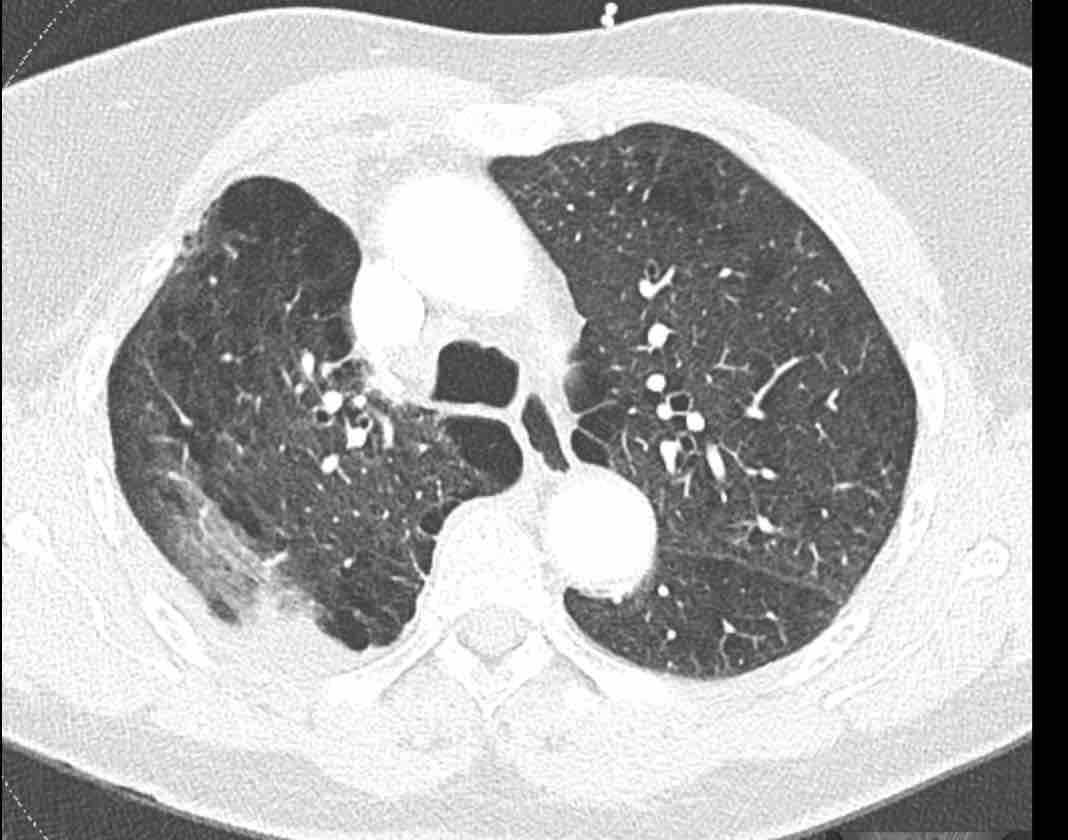

Hình ảnh

Cuộn qua các hình ảnh.

Phế quản thùy trên, phế quản trung gian và phế quản thùy dưới tiếp tục đi về phía ngoại vi.

Phế quản thùy giữa kết thúc tại vị trí đặt các ghim phẫu thuật.